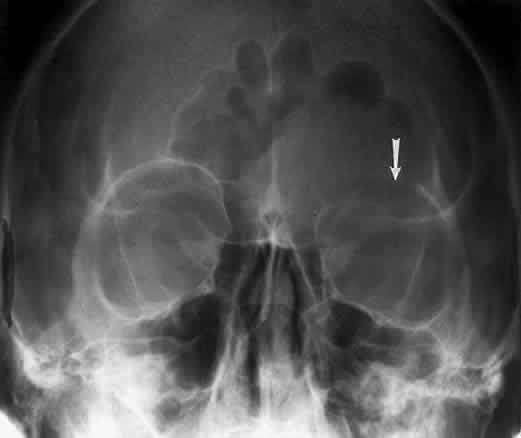

The posterior segment of the lateral wall courses posterior medially and can be seen in anterior projections such as the Caldwell view. This view allows direct visualization of the greater sphenoid wing contribution to the lateral wall. Bone density changes in the greater wing of the sphenoid, such as from a meningioma, can be detected. Fractures of the lateral orbital wall can occur from blunt trauma to the malar prominence. The zygomatic complex fracture (tripod) results from separation of the zygomatic-frontal, zygomatic-temporal, and the zygomatic-maxillary sutures. These fractures are associated with an inferior displacement of the malar prominence and a rounded lateral canthus (Figs. 8 and 9).

Fig. 8. A zygomatic complex fracture (tripod) after blunt trauma to the right cheek. Note the right zygoma is inferiorly displaced. (a, zygomatic-frontal suture separation; b, orbital rim disruption; c, opacification of maxillary sinus)

Fig. 9. Bilateral zygomatic complex and LeFort II fracture after reduction using fixation plates. Caldwell projection shows good alignment of orbital margin and zygomatic bones.